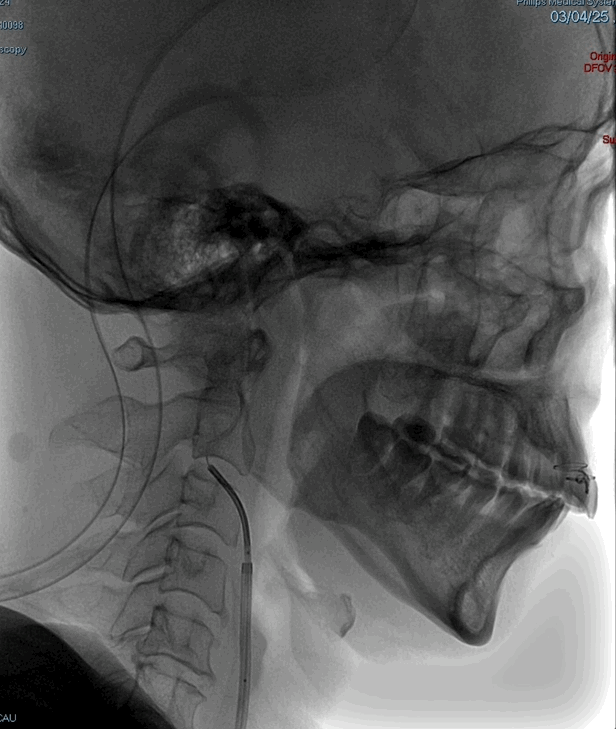

术前DSA造影显示左侧颈内动脉自起始段闭塞,C6眼段以上供血区由颈外动脉眼动脉反向代偿供血,左侧大脑中动脉供血区由前交通动脉代偿供血。

高分辨核磁:颈动脉斑块分析提示左侧颈内动脉全程管径缩窄,C1及C4-C5段不稳定斑块形成伴管腔闭塞。

造影后引导下,以0.014in×185cm 微导丝小心通过右侧颈内动脉C1段闭塞处至C3段。随后以0.014in×300cm 微导丝在SL-10微导管支撑下通过闭塞段,成功进入大脑中动脉M1段。